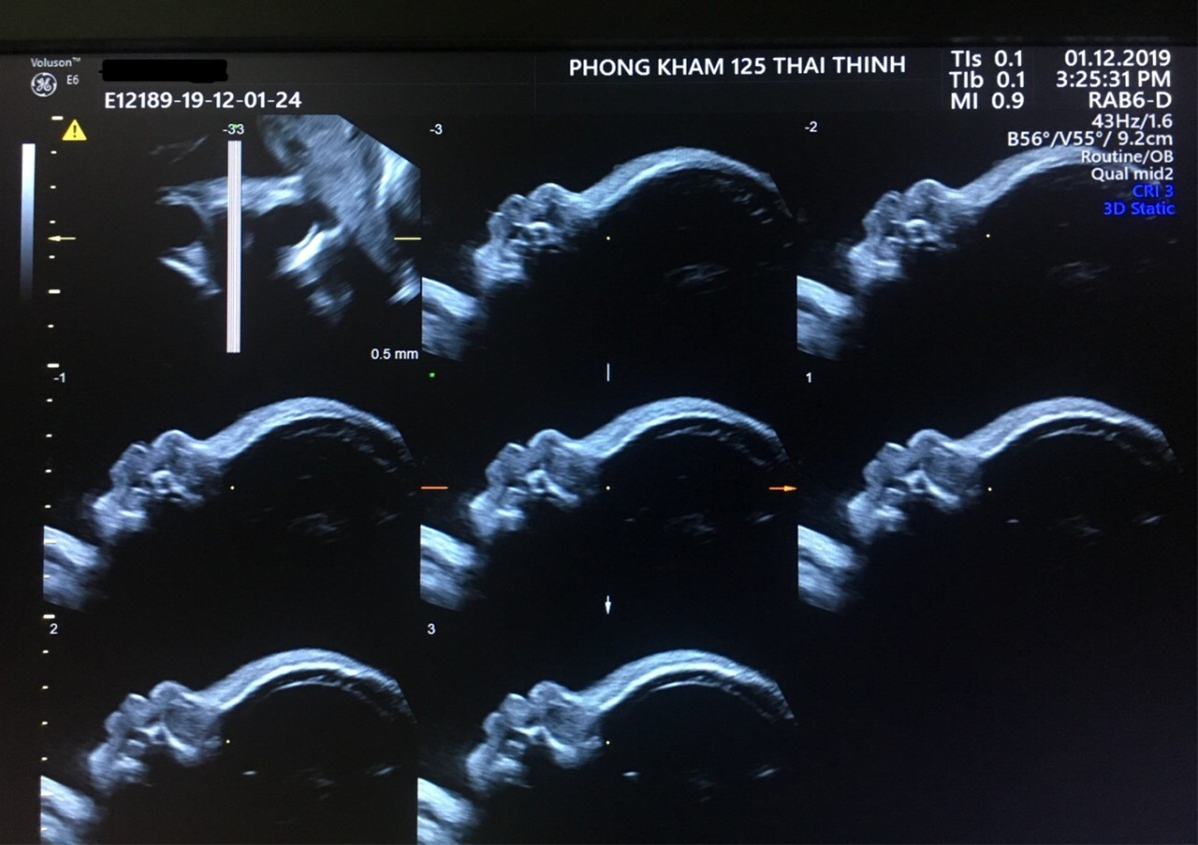

- Siêu âm hình thái 4D chuyên sâu (18–22 tuần), kiểm tra tổng thể não, hộp sọ, tim thai, tứ chi, khuôn mặt, nội tạng,...

Sau mốc này, xương mũi có thể được theo dõi lại trong siêu âm hình thái ở tuần 18–22, khi khuôn mặt và các cấu trúc xương phát triển đầy đủ hơn. Trong một số trường hợp cần thiết, bác sĩ có thể đo xương mũi ở các lần siêu âm tiếp theo để theo dõi sự tăng trưởng hoặc xác định lại khi kết quả trước đó chưa rõ ràng.

Xương mũi phát triển không đồng đều qua các lần siêu âm

- Dấu hiệu trẻ chậm tăng trưởng, không dài ra theo tuổi thai.

- Có thể là bất thường hình thái cần theo dõi sát.

- Bác sĩ thường kết hợp với các chỉ số khác như NT, NB, xương đùi, chu vi đầu (HC), xét nghiệm NIPT…